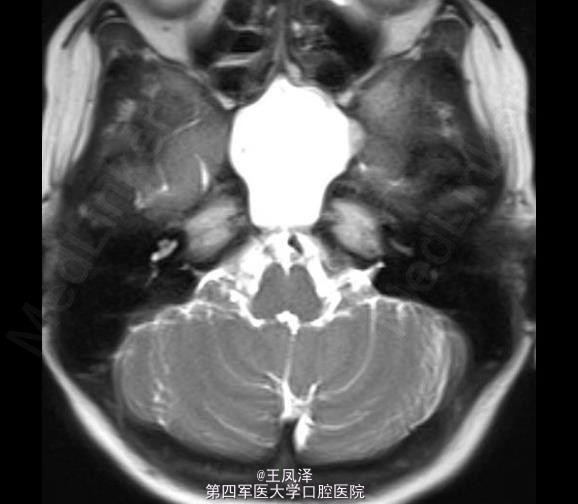

蝶窦粘液囊肿一例

女性,20 岁,在 18 个月大时诊断为自闭症和智力迟钝,目前发生多次抽搐现象,可能为癫痫发作。